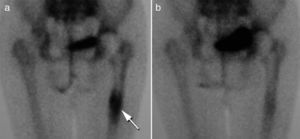

Presentamos el caso de una mujer de 83 años con antecedentes de osteoporosis, posmenopáusica en tratamiento semanal con bifosfonatos y aporte diario de calcio y vitamina D y fractura de cadera derecha a los 64 años, intervenida con colocación de prótesis cementada. Acudió a consulta por coxalgia derecha mecánica, con claudicación en la marcha de meses de evolución. En la exploración destacaron limitación y dolor a la rotación de la cadera derecha. Se realizó una radiografía de cadera (fig. 1) y, ante la sospecha de movilización aséptica de la prótesis, se realizó una gammagrafía ósea en 3 fases que muestra captación en el tercio distal (fig. 2a), confirmando así el diagnóstico. Iniciamos tratamiento con ranelato de estroncio más aporte de calcio y vitamina D. Transcurridos 2 meses, la paciente mejoró significativamente y desapareció la claudicación para la marcha que presentaba con anterioridad. A los 6 meses se repitió la gammagrafía ósea, que mostró una reducción cercana a la normalidad de la hipercaptación isotópica que mostraba al inicio (fig. 2b).

El ranelato de estroncio, utilizado para prevenir fracturas osteoporóticas2, se ha mostrado eficaz para mejorar la osteointegración de prótesis en animales3,4. Sin embargo, no se conocen hasta la fecha estudios que evalúen sus efectos en humanos para esta misma finalidad. Por tanto, el caso aquí presentado aporta datos que sugieren que el ranelato de estroncio puede resultar benéfico para la osteointegración en una prótesis de cadera. La mejoría sustancial de los síntomas apenas 2 meses de haber iniciado el tratamiento junto a la normalización de la gammagrafía ósea a los 6 meses resultan prometedores y sugieren su potencial aplicación en cirugía ortopédica.